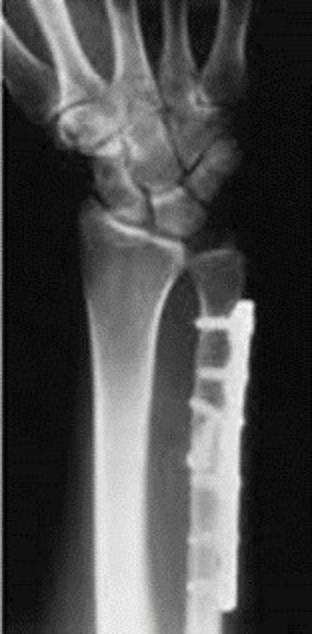

目前標準手術方式為使用「互鎖式鈦合金鋼板」固定,不僅減少螺絲鬆脫風險,對骨質疏鬆者尤其有利,還可縮短固定時間,加快進入復健期,避免關節僵硬。

術後恢復與健保補助

高鈞彥說,若骨折使用互鎖式鋼板固定穩固,可立即啟動手腕活動訓練,不需傳統石膏固定6至8週,甚至一週內即可恢復文書等輕度工作。好消息是,健保已將遠端橈骨與近端肱骨骨折納入骨鬆治療給付範圍(以往僅限脊椎與髖部)。醫師提醒,民眾符合條件者都可與專業醫師討論,個人化的骨質疏鬆治療計畫。